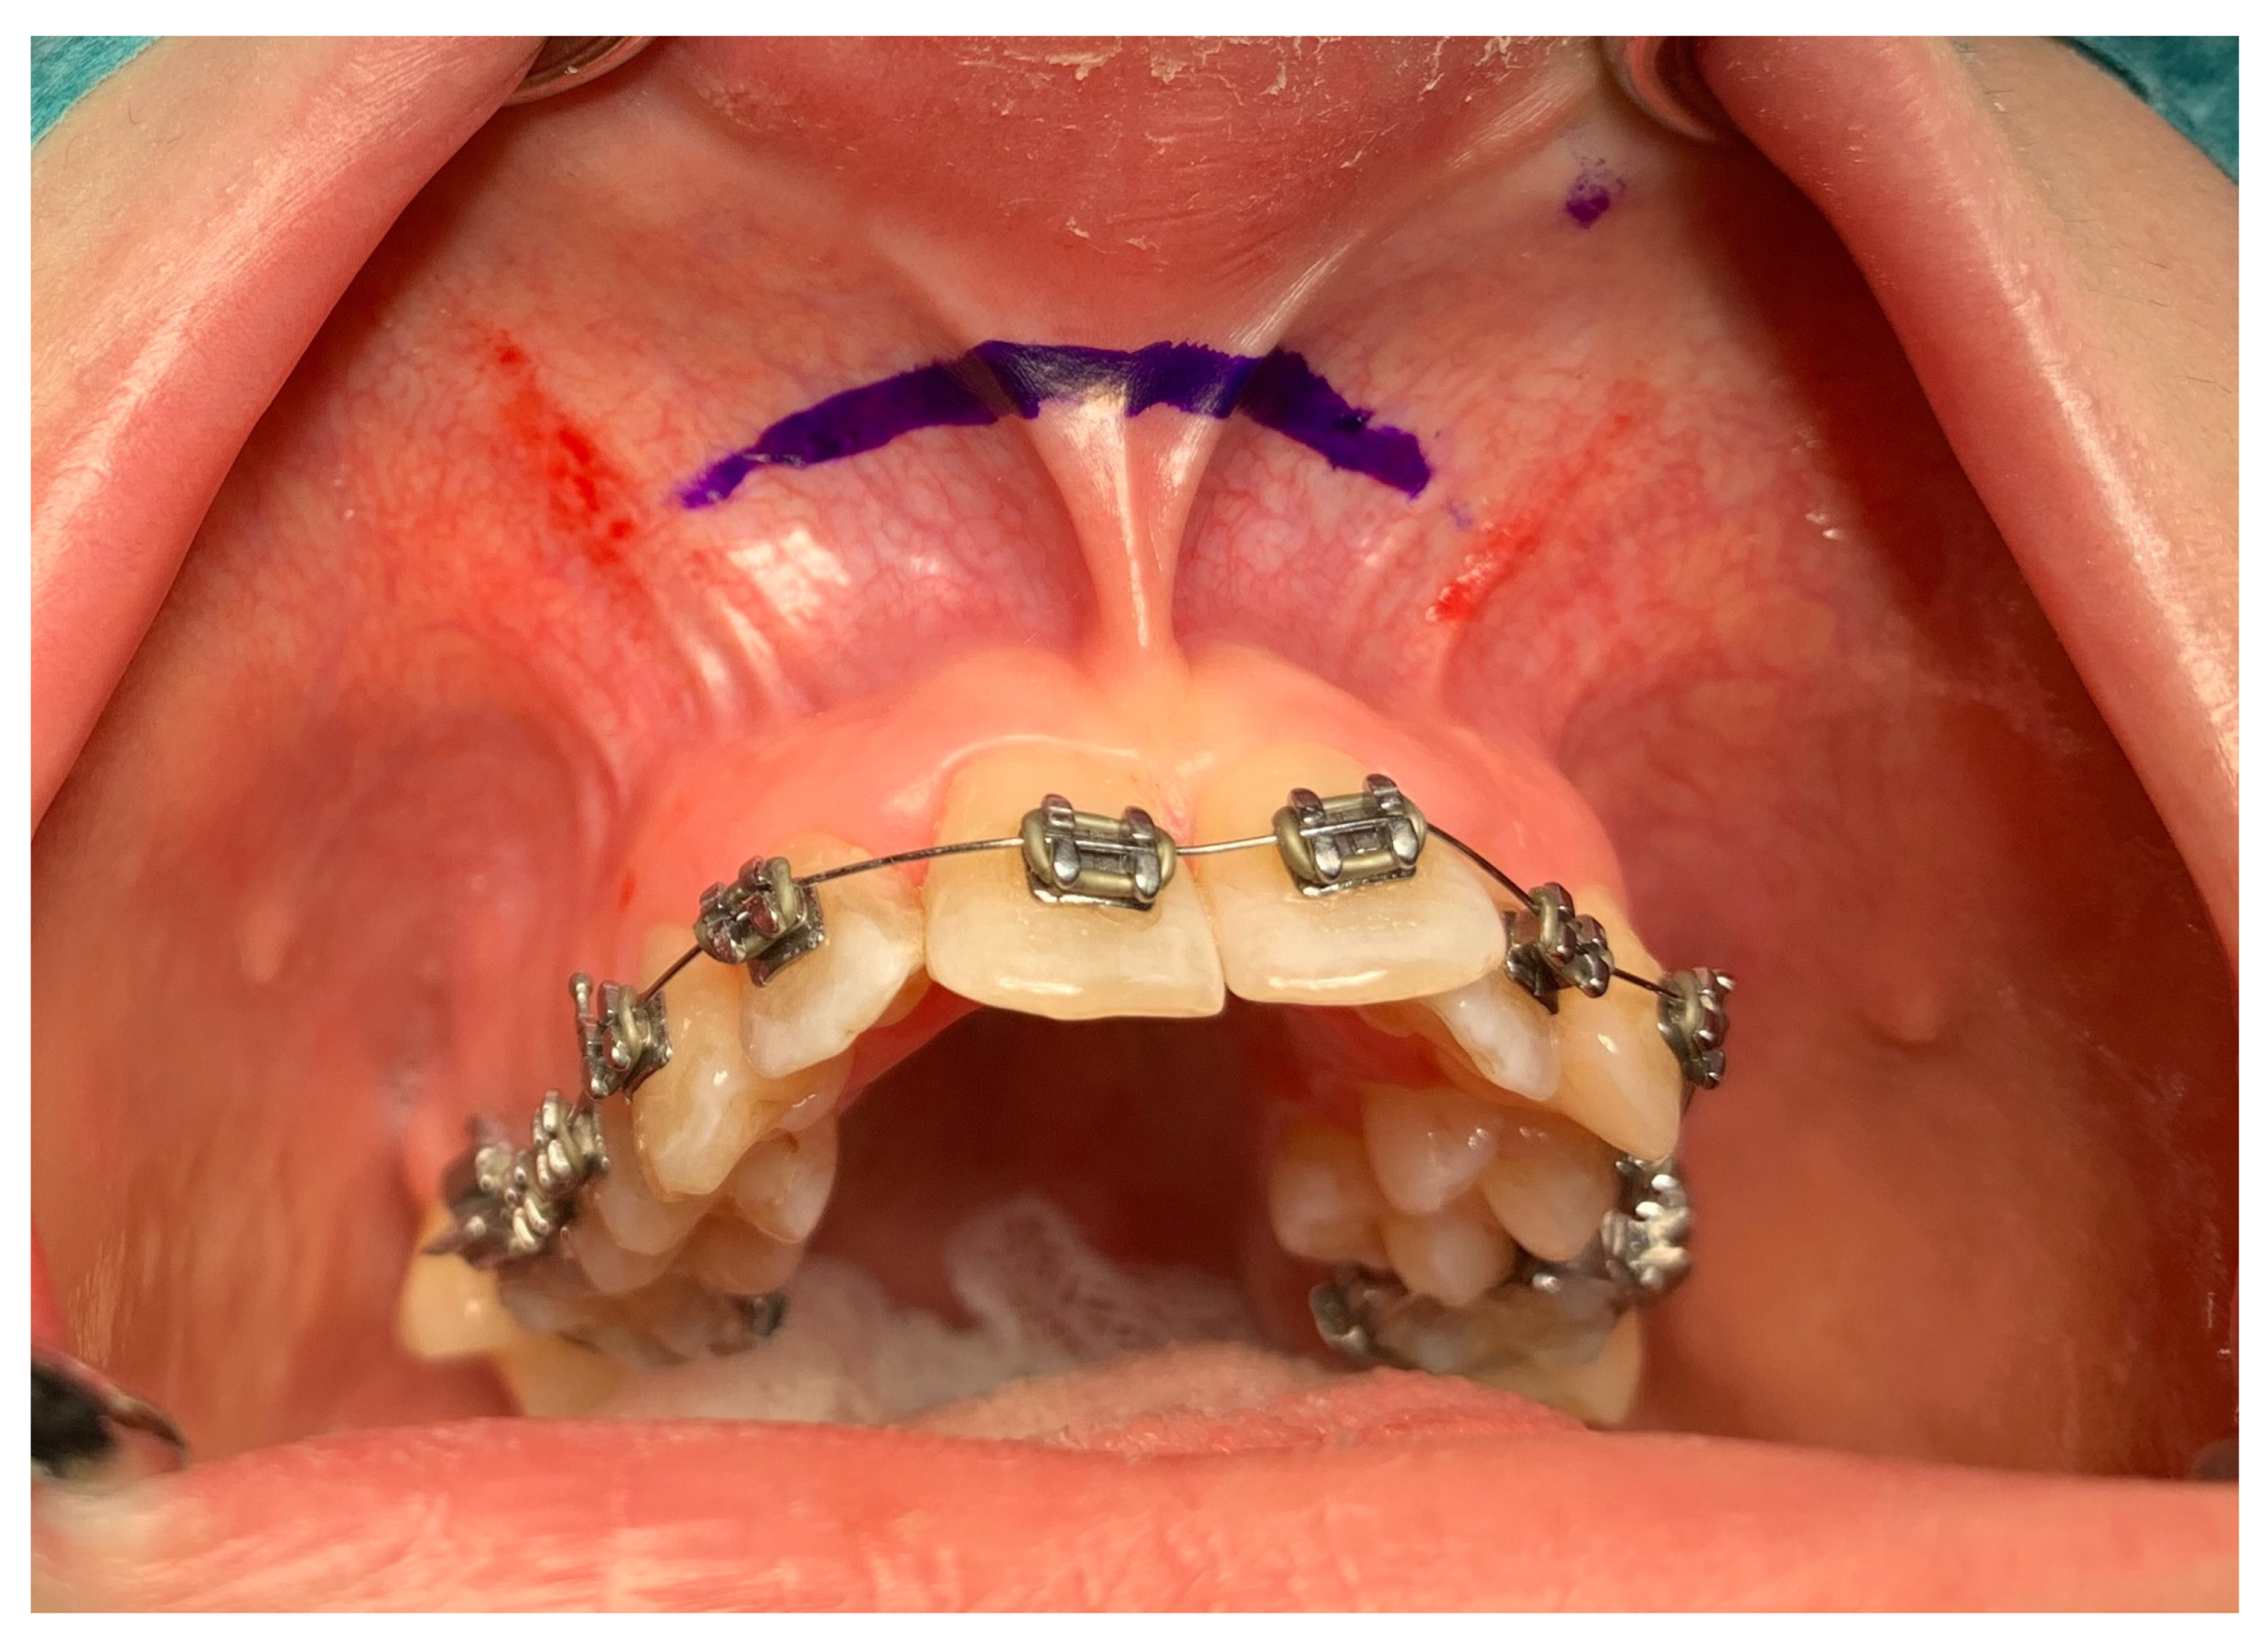

| No possibility of distraction—1 case | Maxillary incisor root resorption—2 cases |

| Palatal mucosal necrosis—2 cases | Bone loss/lack of adhesion in the distraction gap—5 cases |

| Perforation of the maxillary alveolar process caused by the distractor—1 case | Maxillary incisor necrosis—2 cases |

| Asymmetric distraction—5 cases | |

| 9 cases (4.86%) | 9 cases (4.86%) |